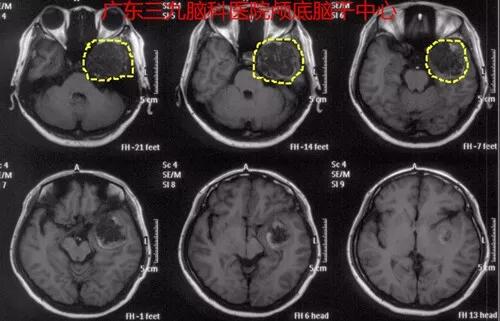

42岁的宫女士3天前突然出现头痛伴呕吐,当地医院影像检查发现中颅窝占位性病变,转诊至广东三九脑科医院,神经外一科专家接诊后完善头颅MRI及CTA检查,诊断:左侧中颅窝囊状占位性病变,这就是引起她头痛呕吐的“元凶”。

图1:左侧中颅窝囊状占位性病变,呈低密度为主,囊壁示多发斑点,斑片状高密度钙化灶。

图3:术后MR报告:左侧颞底占位病变切除术后改变,原病变已切除